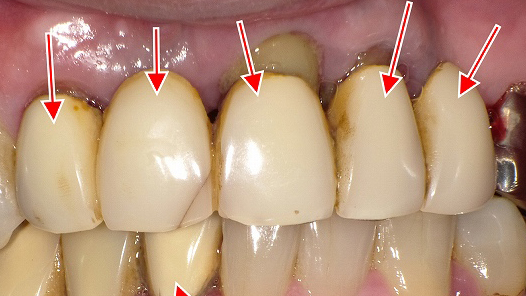

この写真は、**右上1番・2番・3番(中切歯・側切歯・犬歯)にメタルボンド冠(陶材焼付鋳造冠)**が装着されている症例です。矢印の部分に注目すると、いくつかの審美的および歯周的な問題が見られます。

🔍 観察ポイント

- 補綴物の種類:右上前歯3本にメタルボンド冠が装着されています。内側は金属フレーム、外側が陶材(セラミック)です。

- ブラックマージン(黒い境界線):歯と歯ぐきの境目に黒いラインが見られます。これは金属のフレームが歯肉退縮により露出しているためです。

- 歯肉退縮:右上1番・2番・3番で歯ぐきが下がり、根面(歯根表面)が露出しています。露出した部分は黒く変色しており、象牙質やセメント質の着色、または金属イオンの影響が考えられます。

- 審美的不調和:補綴物の色調と隣接天然歯のトーンが異なり、特に歯頸部の黒ずみが目立ちます。

⚠️ 想定される原因

- 経年的な歯肉退縮(加齢・ブラッシング圧・歯周病など)

- メタルボンドの金属フレームが光を透過しないため、歯肉が黒く見える(メタルシャドウ)

- 根面の露出による歯根象牙質の変色

- 金属成分(Ni・Crなど)が歯肉に沈着するメタルタトゥーの可能性もあり

💡 審美改善の選択肢

- オールセラミック冠(ジルコニア冠など)への置き換え

→ 金属を使用しないため、ブラックマージンや歯肉の黒ずみが改善されます。 - 歯肉移植(結合組織移植)による歯肉ラインの回復

→ 退縮部分をカバーし、より自然な歯肉形態を取り戻すことが可能。